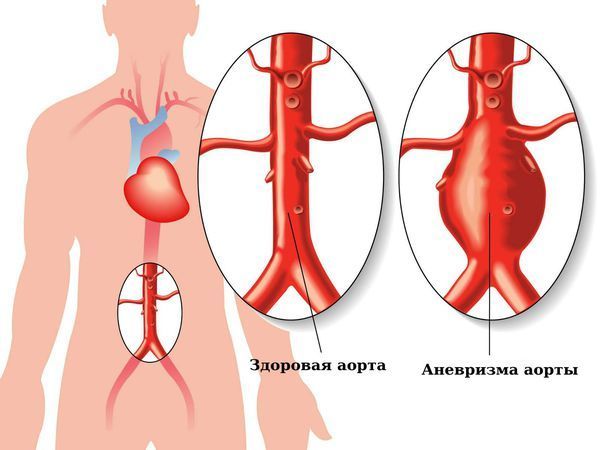

- Дегенеративными поражениями крупных сосудов. К примеру, аневризма инфраренального отдела аорты (нижнего сегмента брюшной аорты) с разрывом может приводить к внутреннему кровотечению [5].

Аневризма брюшной аорты